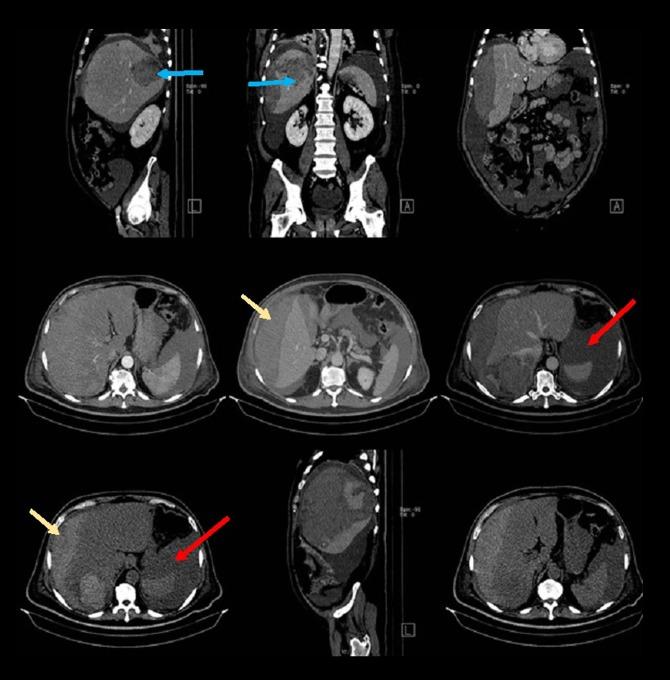

BACKGROUND Gastrointestinal stromal tumors (GISTs) are rare gastrointestinal neoplasms. The spontaneous rupture of a jejunal GIST is very rare and spontaneous rupture of liver metastasis from an intestinal GIST is even rarer with only a few cases reported in the literature. CASE REPORT In this article, we reported a case of spontaneous rupture of a liver metastasis from a malignant jejunal GIST that presented with active tumoral bleeding, hypovolemic shock, and hemoperitoneum. The patient was successfully treated with arterial embolization of the tumor. CONCLUSIONS In appropriately selected patients, arterial embolization appears to be an effective safe treatment for a GIST metastasis rupture.